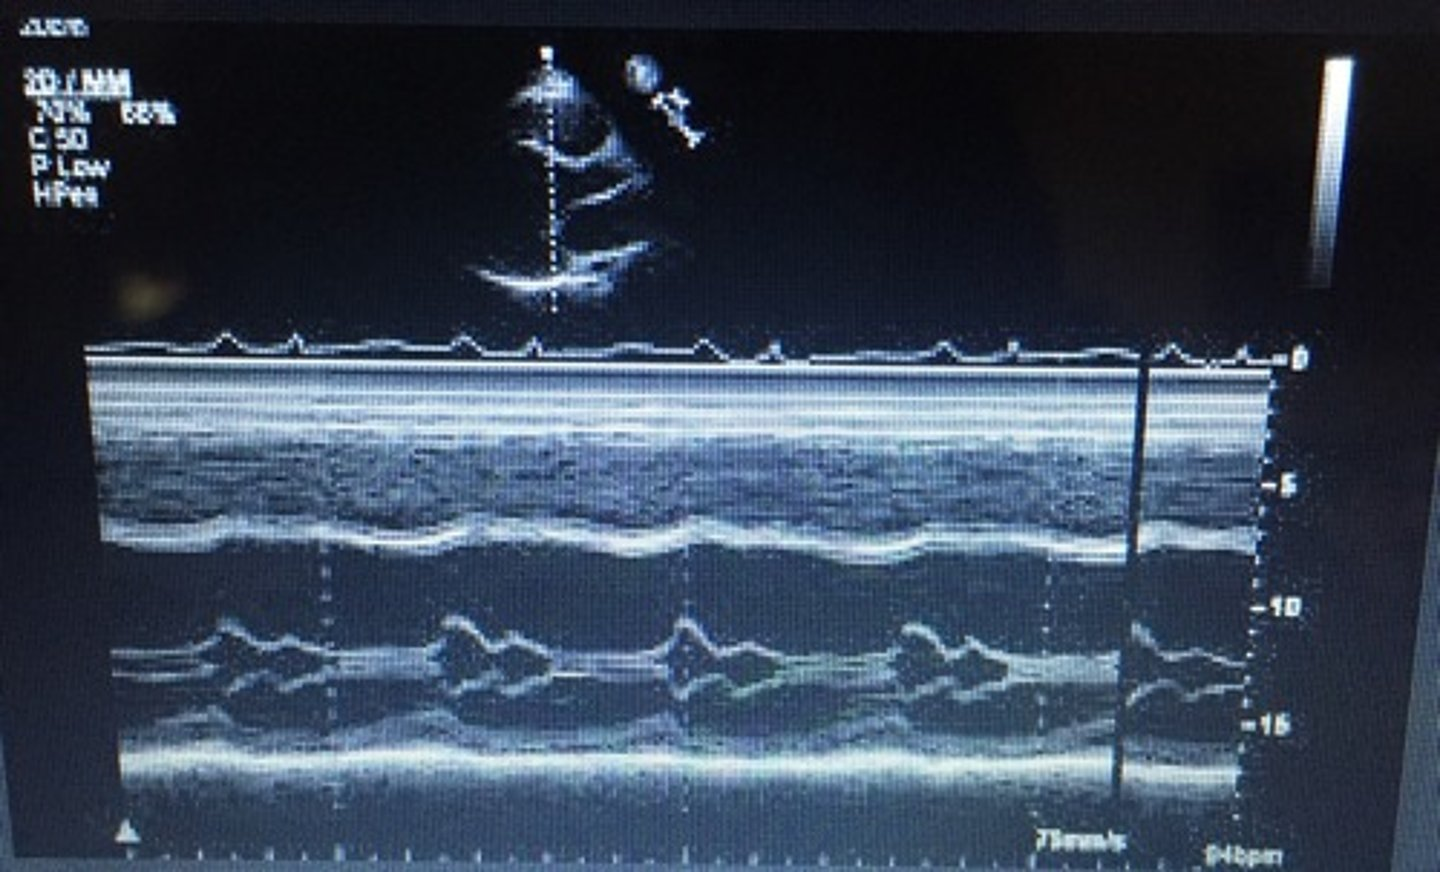

extra hump between A-C; commonly seen with dilated cardiomyopathy and LV dilation; increased LVDP and LA pressure; decreased EF% and EPSS is >10mm

B-Bump/B-Notch/ A-C Shoulder